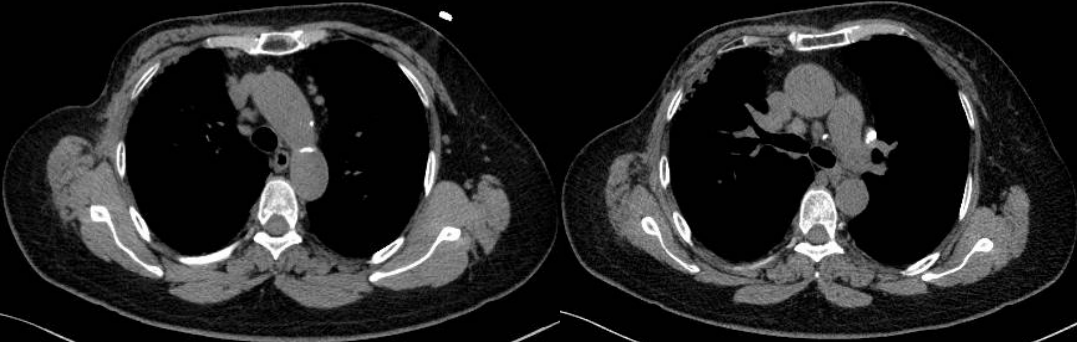

PET/CT示:雙側(cè)鎖骨上、縱隔、胸骨后、雙肺門(mén)、雙側(cè)肋骨旁、腹腔、腹膜后、盆腔及左側(cè)腹股溝見(jiàn)多枚代謝異常增高淋巴結(jié),較大者約3.4×2.1cm,SUVmax約20.7。

PET/CT診斷:考慮結(jié)節(jié)病,建議病理檢查。

此例患者由于乳腺癌的病史,臨床初步懷疑轉(zhuǎn)移。PET/CT顯示縱隔、肺門(mén)淋巴結(jié)腫大,且呈對(duì)稱(chēng)性分布,密度均勻,邊界清晰,無(wú)明顯融合,F(xiàn)DG高攝??;此外可見(jiàn)多發(fā)腹盆部,頸部淋巴結(jié)次之,分布較散,體積及FDG攝取小于縱隔和肺門(mén)淋巴結(jié),也不是乳腺癌術(shù)后易轉(zhuǎn)移的部位。綜上考慮符合結(jié)節(jié)病表現(xiàn),最終得到病理證實(shí),患者因此避免了不必要的抗腫瘤治療。